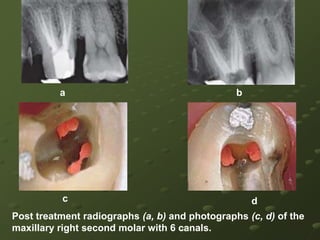

A Five-canal Maxillary Second Molar*May 2007, Volume 4, No.5  Journal of US -China Medical Science , ISSN1548-6648 USACASE REPORTThe patient was a 35 years old male who presented with a severe spontaneous pain in the maxillary right area which had been constant for one day. The medical status was unremarkable. Clinical examinations revealed that tooth-2 had deep mesio-occlusal caries without pulp exposure and was very sensitive to cold test.

Radiographic examination disclosed an unusual anatomical configuration of the roots, suggesting that four roots might be present.A diagnosis of acute pulpitis was made for tooth-Following local anaesthesia an endodontic access opening was made and the pulp chamber was exposed clearly.

Preoperative radiograph of tooth

Examination of the chamber floor with an endodontic explorer (DG-16) revealed five canal orifices1.mesiobuccal canal (MB1),2.mesiobuccal 2nd canal (MB2),3.mesiopalatal canal (MP),4.distopalatal canal (DP)5.distobuccal canal (DB)

The orifice of the mesiopalatal canal was large, well formed, and located at the mesiopalatal corner of the pulp chamber.The distopalatal canal was also large and well developed and more distal to the chamber than a single palatal root would be expected. The MB2 orifice was found nearly on the imaginary line between the MBl and MP orifice, and about 1.5mm palatal to the MBl orifice

Occlusal view of seating of master point, displaying five root canal orificesOcclusal view of the access opening showing MB1, MB2, DB, and MP canal orifices

All canals were easily negotiated, and the working length was determined by using electronic apex locator Root ZXThe root canals were cleaned and shaped using K-type files and Gates Glidden drills #2, #3, and #4 with passive step-back technique.Apical preparations in the buccal canals were enlarged to a master file size of 30, and in the palatal canal to size of 45.

The root canals were copiously irrigated with 3% H2O2 solution.Then the canals were obturated with AH-Plus sealer and gutta-percha using a lateral compaction technique. A temporary restoration with IRM was placed and a permanent restoration was advised. At the 3 month recall examination, the tooth was asymptomatic with normal periapical

Post obturation occlusal view of the pulp chamber floor showing all five root canal orificesPostobturation radiograph (RVG) displaying five root canals